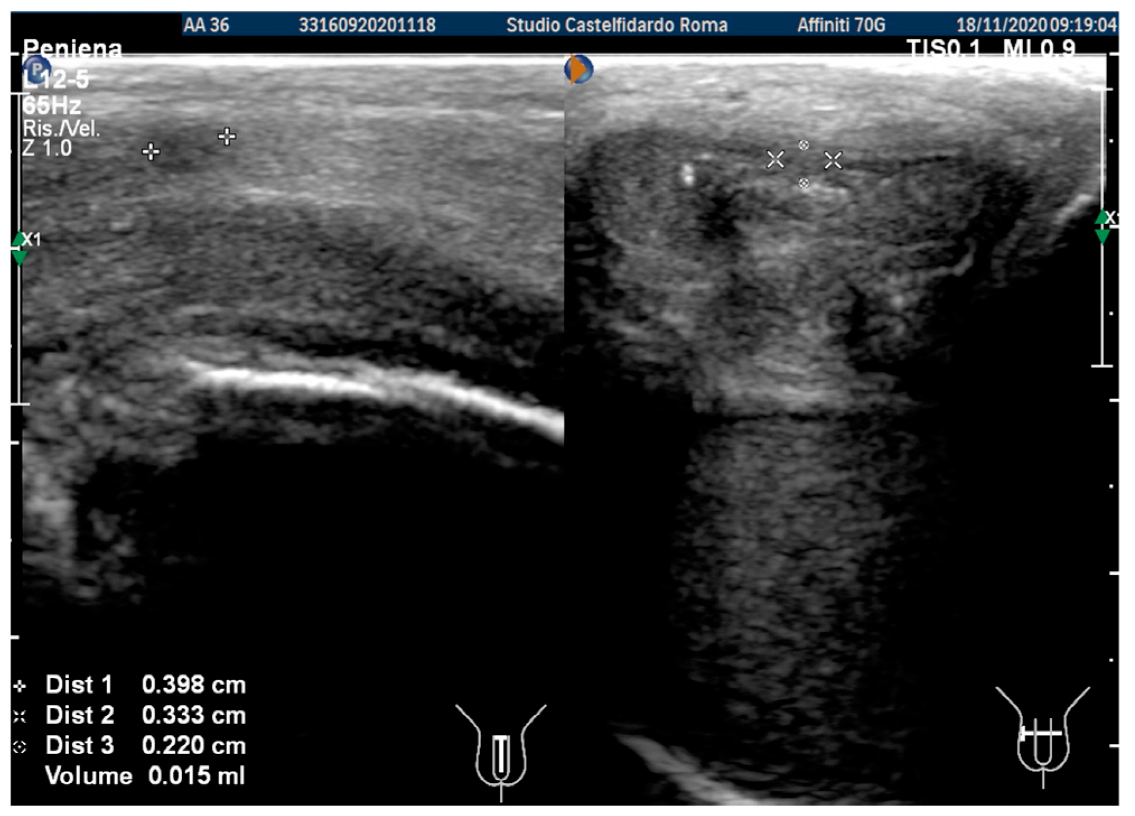

| 2 | 32 years | lichen sclerosus, chronic prostatitis | Proximal third | (A) 16.4 × 8.27 × 3.09 mm volume = 219 mm3 | (A) 10-degree left curvature | (A) score 3 | (A) score 26 | 2 years and 9 months | orally: Silymarin 400 mg + Ginkgo biloba 250 mg + Propolis 600 mg + Bilberry 160 mg + Vitamin E 800 IU/once a day, for 33 months. + topically: Propolis creme/twice a day/for 33 months. + peri-plaque penile injections: Pentoxifylline 100 mg (30 G needle) every 15 days for 6 months, and then monthly for 12 months, and then 1 injection every other month. for 12 months (total = 30 injections) |

| (B) No plaque detected | (B) None | (B) score 0 (after six months) | (B) score 28 | ||||||